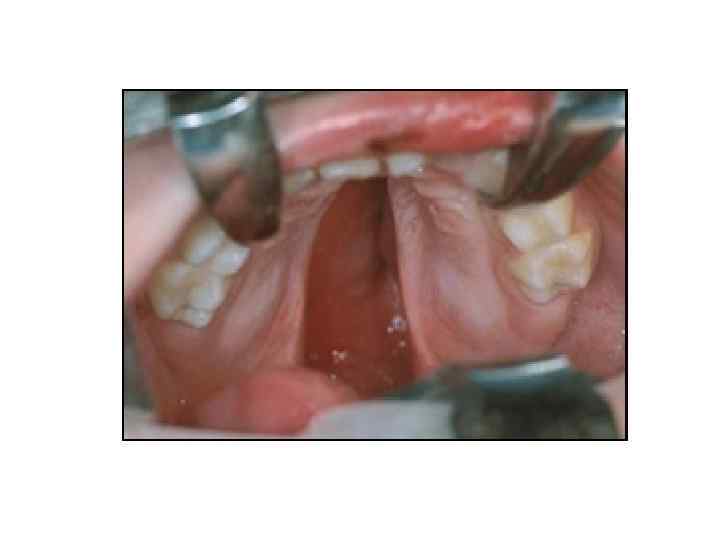

• • • ПОЛОСТЬ РТА (CAVITAS ORIS) ГЛОТКА (PHARYNX) ПИЩЕВОД (ESOPHAGUS) ЖЕЛУДОК (VENTRICULUS, • • • ПОЛОСТЬ РТА (CAVITAS ORIS) ГЛОТКА (PHARYNX) ПИЩЕВОД (ESOPHAGUS) ЖЕЛУДОК (VENTRICULUS, GASTER) ТОНКАЯ КИШКА (INTESTINUM TENUE) ТОЛСТАЯ КИШКА (INTESTINUM CRASSUM) КРУПНЫЕ ПИЩЕВАРИТЕЛЬНЫЕ ЖЕЛЕЗЫ- ПЕЧЕНЬ (HEPAR), ПОДЖЕЛУДОЧНАЯ ЖЕЛЕЗА (PANCREAS) СЛЮННЫЕ ЖЕЛЕЗЫ